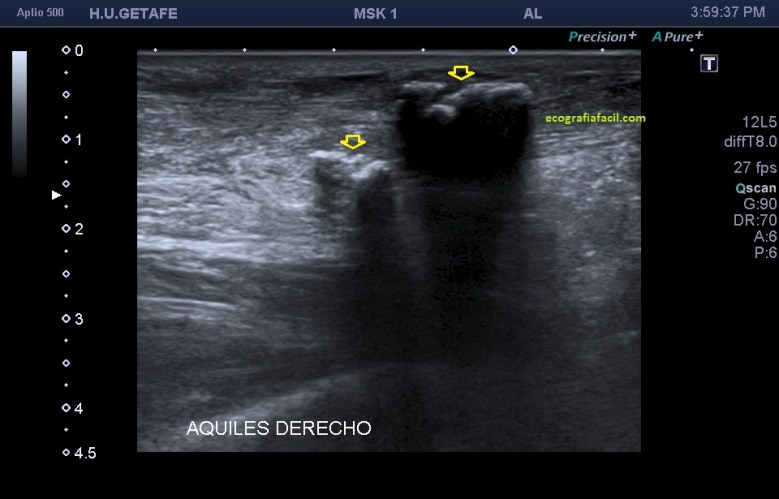

Si observamos la bursitis retroaquílea de la imagen 11(flechas amarillas), además la exóstosis de la imagen 13 y deformidad en la piel, observable sin ecografía podemos estar ante un síndrome de Haglund de esos de libro…y tendremos una imagen ecográfica como la de la imagen 14.

Como has visto en la imagen 1, la bursa retroaquílea no debe verse, ese receso debe tener como mucho una mínima cantidad de líquido, que como digo es normal, pero no lo que observamos en la imagen 11 donde vemos una imagen heterogénea ocupando esa región.